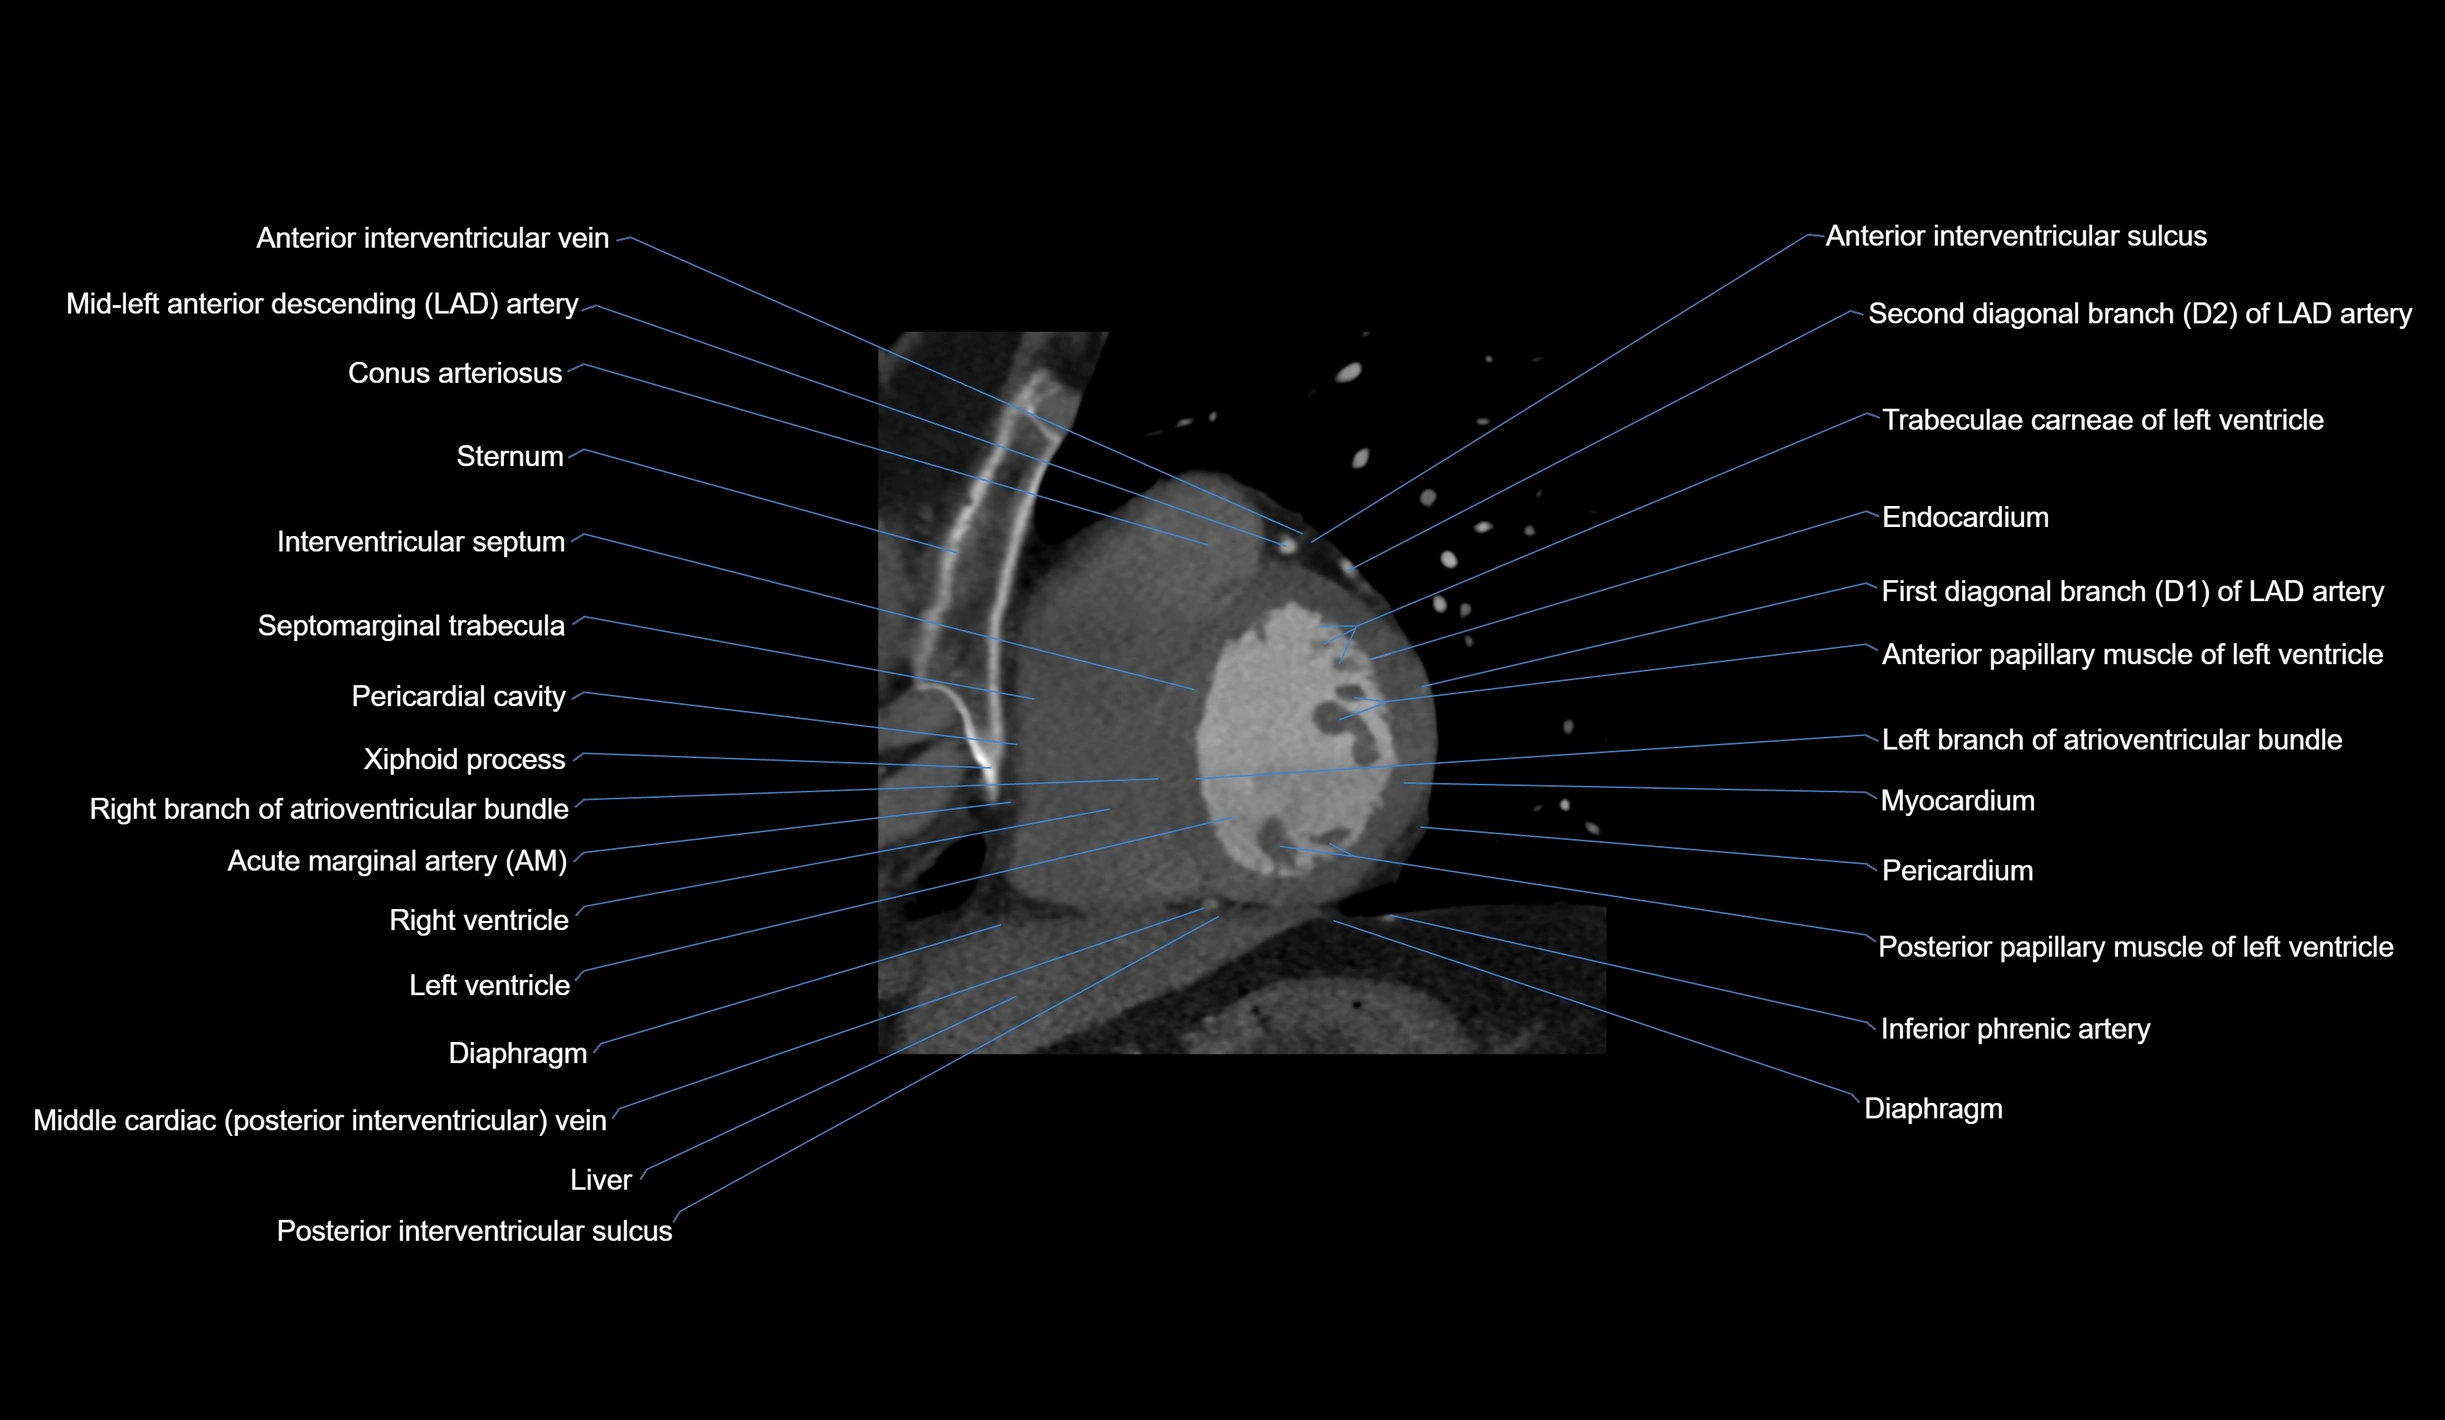

- Acute marginal artery (AM)

CT Appearance

CT Coronary Angiography (CCTA):

-

Best non-invasive modality for acute marginal artery visualization

Shows origin, course along the acute margin, and right ventricular branches

Detects stenosis, occlusion, calcified and non-calcified plaques, aneurysm, or anomalous course

Multiplanar reformats and 3D reconstructions help in pre-PCI and surgical planning

Critical for assessing right ventricular infarction risk in RCA disease

MRI image

CT images